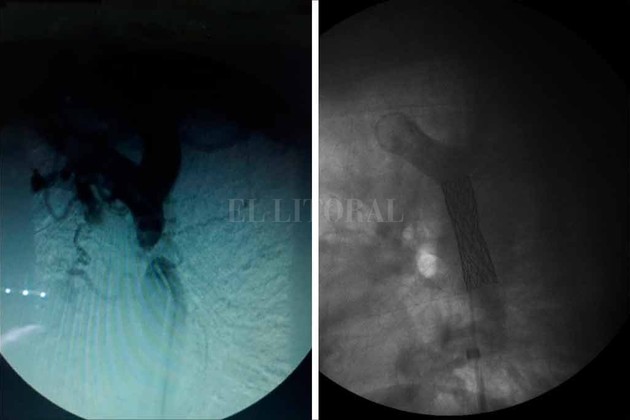

La operación empezó con dos pequeñas punciones: una en la arteria femoral derecha, en la pierna, y otra en la arteria radial en el antebrazo, para poder ingresar los catéteres —son como “tubitos” de 2 milímetros— y llevarlos hacia la zona de la obstrucción, que en el caso de las coartaciones siempre está cerca del ductus arteriosus.

Es el proceso más largo de la intervención y demandó casi 3 horas. El margen de error es mínimo. “Si se perfora la aorta y se produce una hemorragia, el paciente muere en menos de cinco minutos por la pérdida de sangre”, advirtió Birollo, que no pudo participar de la operación, luego de haber realizado muchas gestiones para organizarla, porque la fecha coincidió con un curso de capacitación en Colombia.

Cuando la obstrucción se liberó, comenzó la segunda etapa: “inflar el balón” para ampliar la arteria y colocarle a Darío, con un cateter más grande (1 centímetro), un stent (la angioplastía propiamente dicha). Es una pequeña malla metálica que se utiliza para mantener la arteria abierta y normalizar el flujo sanguíneo. Esta parte llevó unos 40 minutos más.